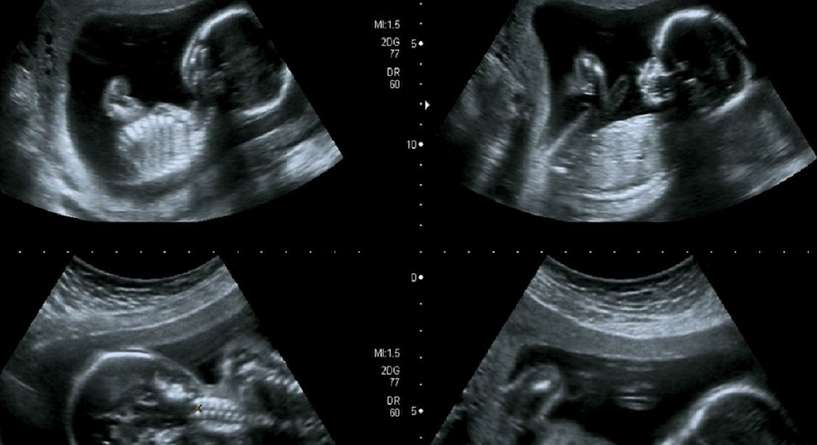

منذ اللحظة التي تعرف فيها المرأة أنها حامل تبدأ بتوقع جنس جنينها. وما من طريقة الا السونار لمعرفة ما اذا كان الجنين ذكرا أم أنثى. ولكن متى يظهر نوع الجنين بوضوح في صورة الموجات فوق الصوتية؟ فلنكتشف سويا في المقال التالي.

التصوير بالموجات فوق الصوتية للجنين هو اجراء ضروري تقوم به المرأة كل عدة أسابيع أثناء حملها للحصول على صور للطفل داخل الرحم ما يساعد الطبيب على معرفة جنس الجنين والتأكد من صحته عبر متابعة نموه وتطوره.

لا يتم تحديد نوع الجنين بوضوح في السونار الا في أواخر الثلث الثاني من الحمل أي بعد اكتمال نمو الاعضاء التناسلية للجنين. ولكن غالبا ما يبدأ الطبيب بتوقع الجنس بعد مرور الأسبوع الثالث عشر من الحمل حيث يعتمد في توقعاته على تحديد اتجاه الحديبة التناسلية، ففي حال كان اتجاهها إلى الأعلى فهذا يعني أن الجنين ذكر، أما إذا كان اتجاهها للأسفل فهذا يدل على أن الجنين أنثى. ولكن من الضروري الاشارة هنا الى أن هذه الطريقة قابلة للخطأ وغير مؤكدة مئة في المئة، لذلك يفضل العديد من الاطباء الانتظار الى الشهر الرابع او الخامس قبل الافصاح للاهل عن جنس الجنين.

يحدث في بعض الأحيان أن يتخذ الجنين وضعية لا تسمح للطبيب بمعرفة جنسه عبر السونار، مما يجعل الطبيب ينصح المرأة بالعودة بعد عدة أيام لمعاودة اجراء الفحص وذلك تفاديا للوقوع بالخطأ.

تصل نسبة الخطأ في تحديد جنس المولود إلى 40% إن تم الكشف عنها في الثلث الأول من الحمل، بينما تقل هذه النسبة إلى 10% إن تمت في الثلث الثاني، لذلك اطلبي سيدتي من طبيبك ان يقوم باجراء التصوير بالموجات فوق الصوتية في كل مرحلة من مراحل الحمل وذلك للتأكد من جنس الجنين وتجنب حدوث أي خطأ.